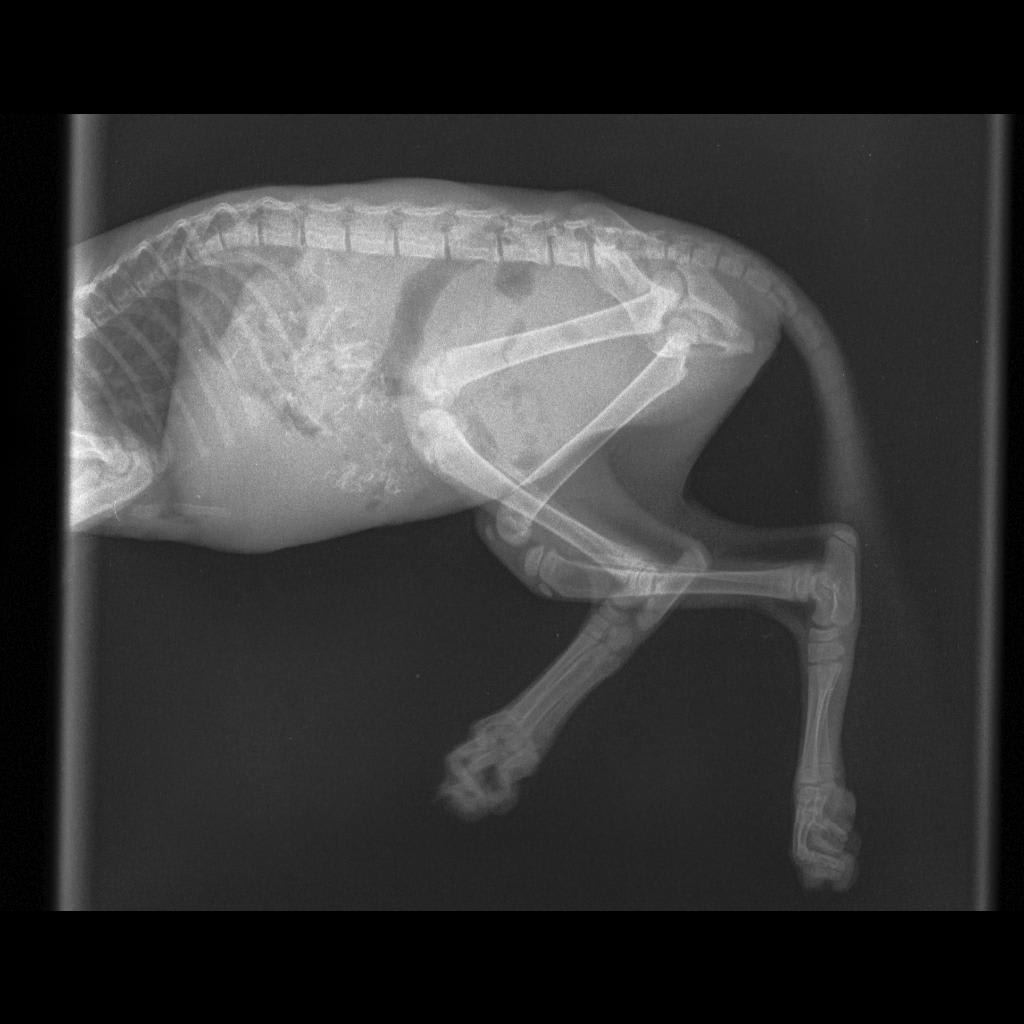

On 13th 2am-3am i hear my kitten screaming from my front gate and and saw her flopping on the ground in pain. I rushed to pick her up and laided her on my lap making her calmed. I stayed awake all night because my kitten will immediately start flopping in pain again. Has brought her to the vet in the evening and the did an xray scan. The vet told me that my kitten left pelvis bone is fractured. But her is limping on her back right leg. The vet said the is nothing much can do to a kitten

In your x-ray I do see the broken pelvis and it looks like it is left sided based on the markers on the x-ray. I'm surprised that she would be putting weight on her left leg, but it's possible that she has another injury that wouldn't be apparent on the x-ray or that the x-ray was mislabeled if this is the case. I would recommend calling or rechecking with the vet - they might want to repeat an x-ray to see if things have changed and if there is something wrong on the other side of her pelvis and leg.